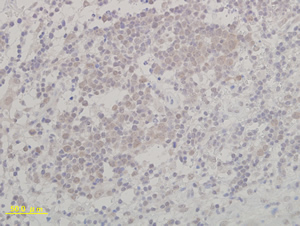

IL-13染色

マウス腫瘍 IL-13